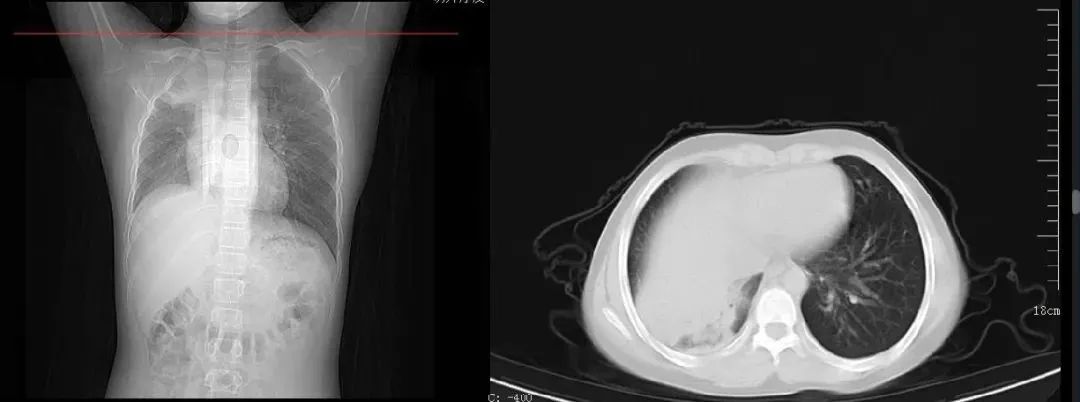

案例二,12歲,男性,確診病例

胸片顯示一側(cè)肺部組織大面積變白

影像所見: 右肺內(nèi)帶見片狀軟組織樣高密度影,右肺野內(nèi)亦可見片狀高密度影,右側(cè)肋膈角變淺變鈍,膈面模糊??紤]右肺部分不張伴胸腔積液可能。